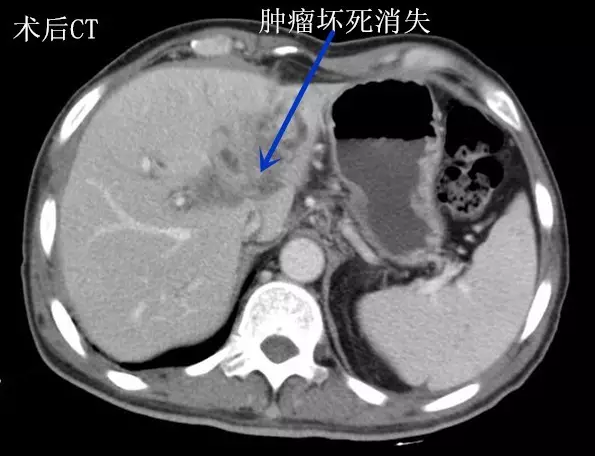

近日,王先生来郑州大学五附院肝胆胰腺外科复诊。黄疸消退,饮食较前明显好转,大小便也恢复正常,体重较前增加5kg。CT显示:肿瘤消失(术后CT图),行T型管造影,胆管通畅(胆管造影图)。王先生说:“手术前,黄人一个;而如今面色红润,能吃能睡,逛街游玩样样行。”